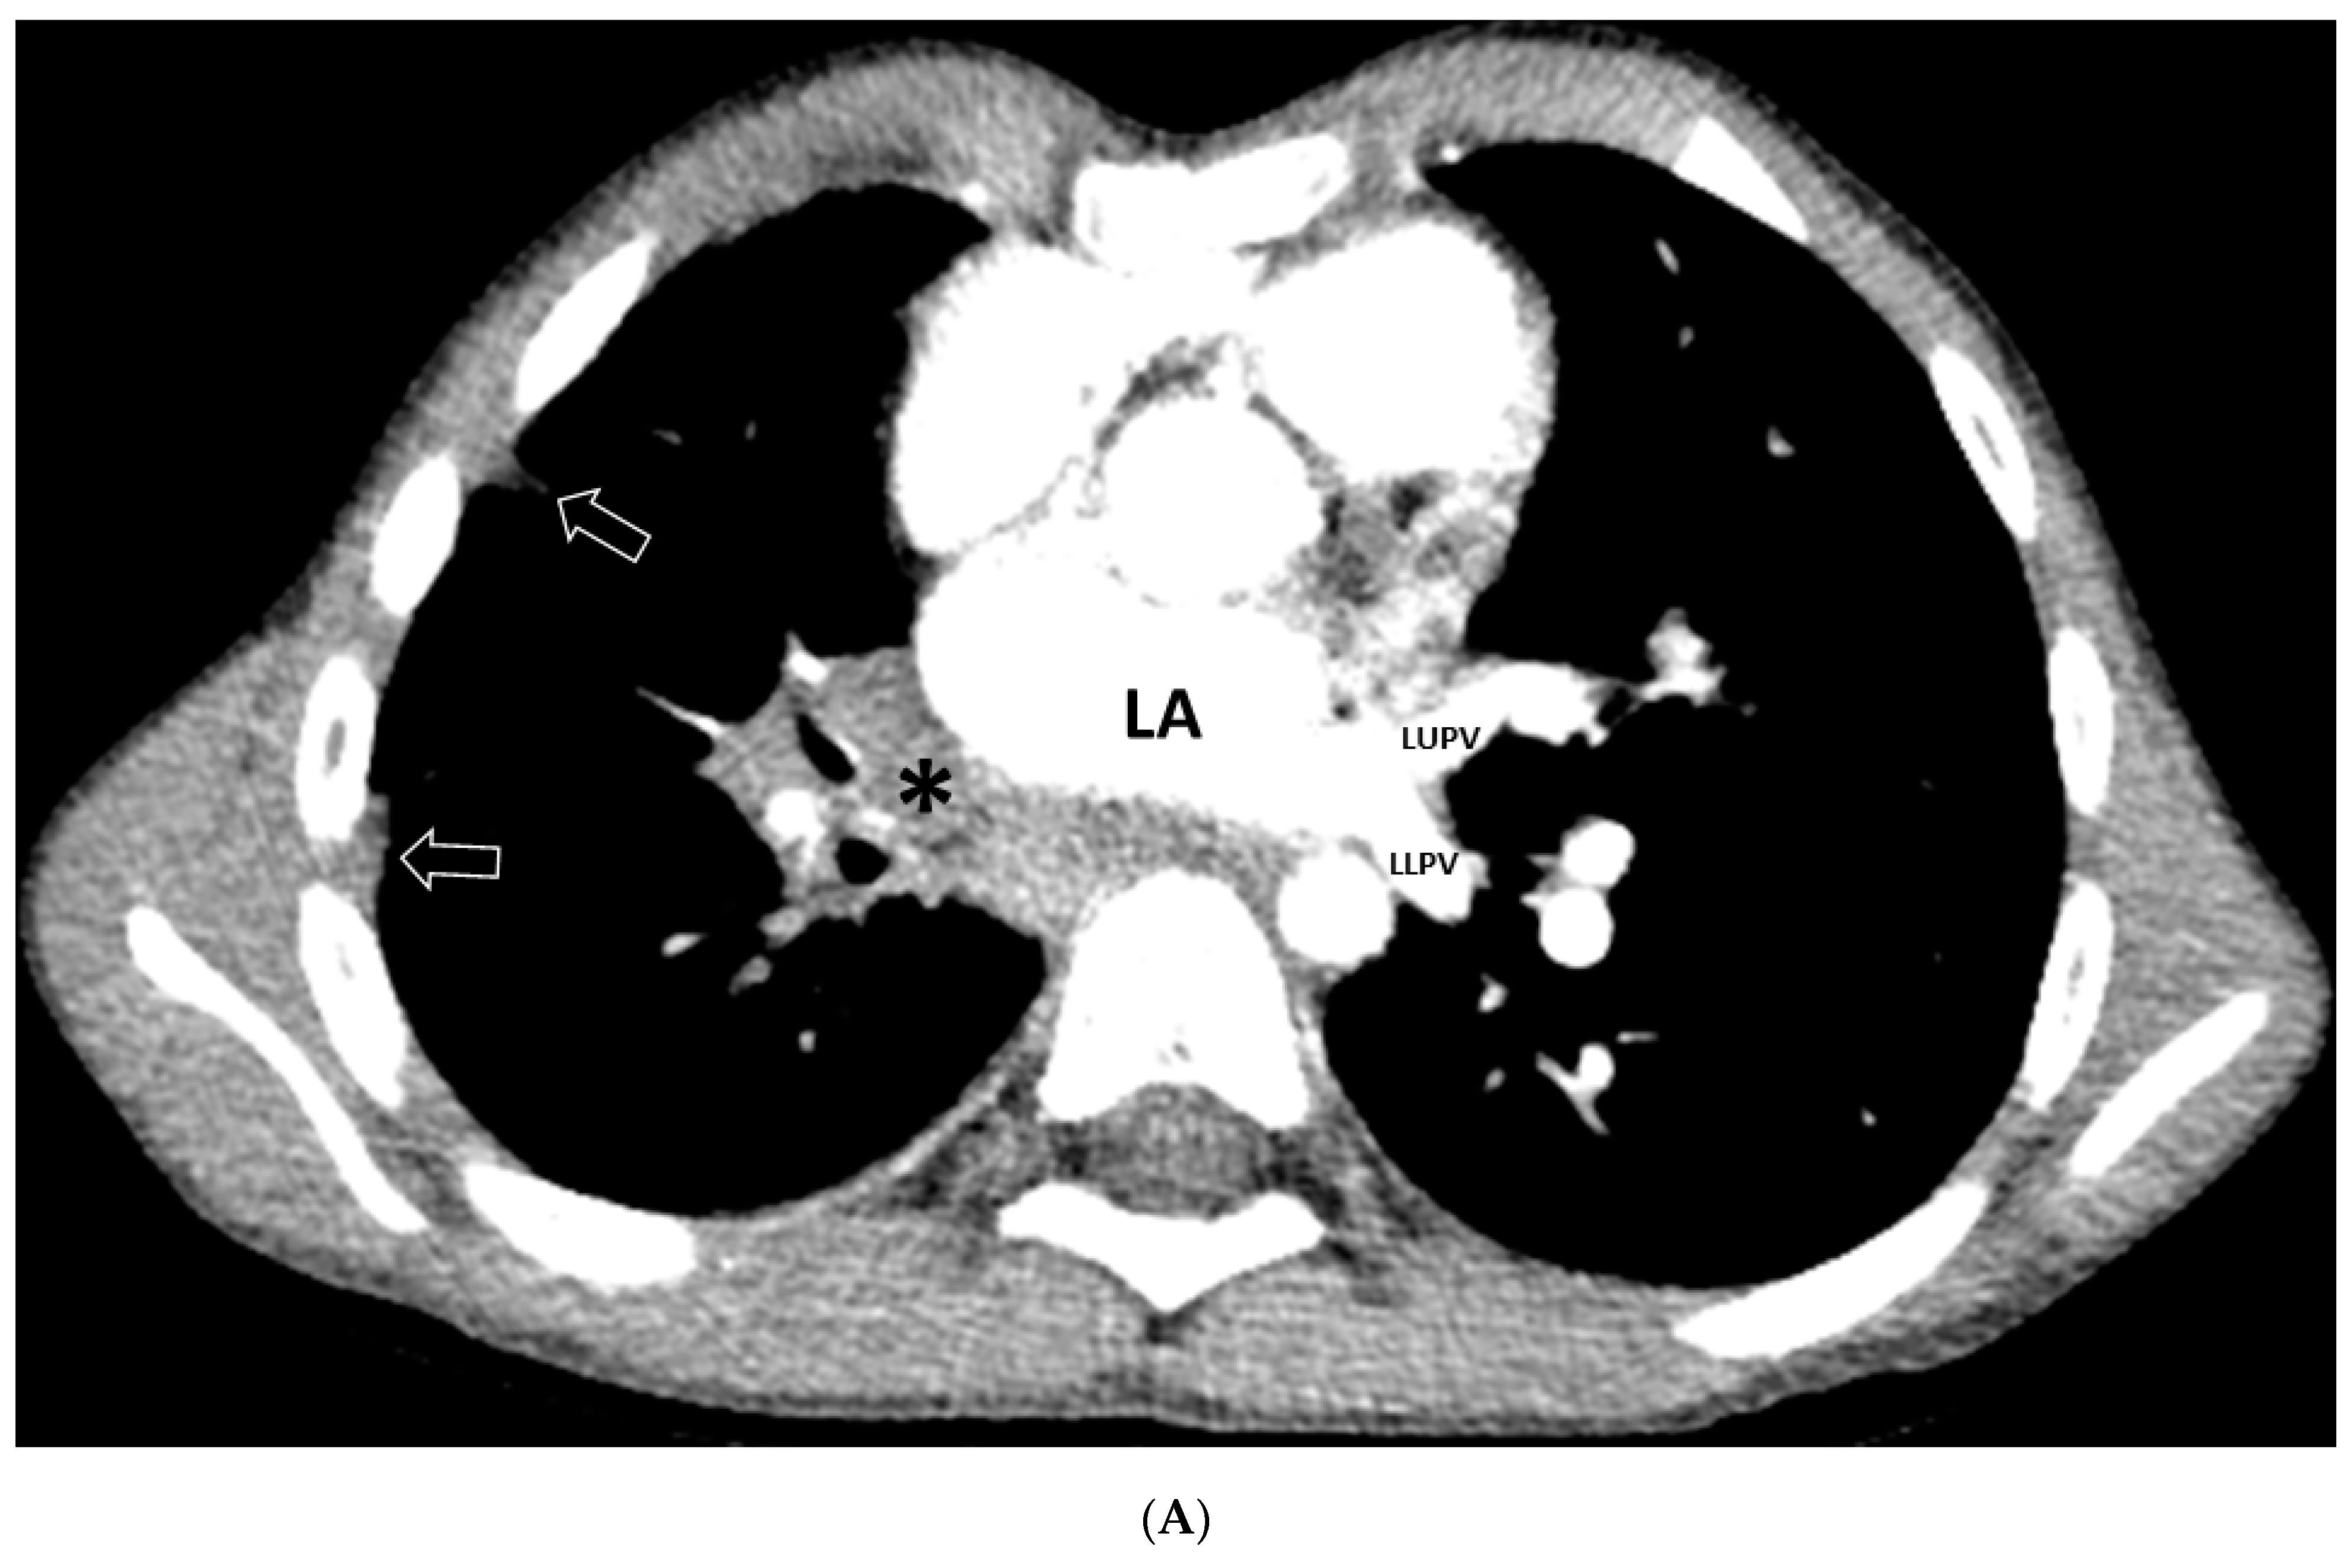

| GGO | 19/20 (95%) |

| Septal Thickening | 7/20 (35%) |

| Pleural Thickening | 17/20 (85%) |

| Mediastinal Mass | 17/20 (85%) |